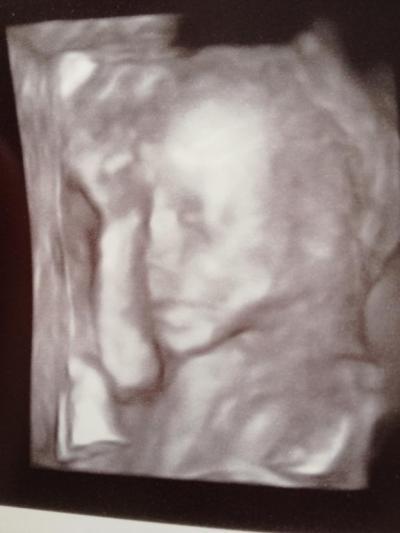

Alles gut, Baby super entwickelt, alles dran was muss :) Bin sooo happy und hab ein 4D Bild bekommen. Kann kaum abwarten bis November ist.

Ah ja, sie wiegt 360g und ist ca 27cm gross :)